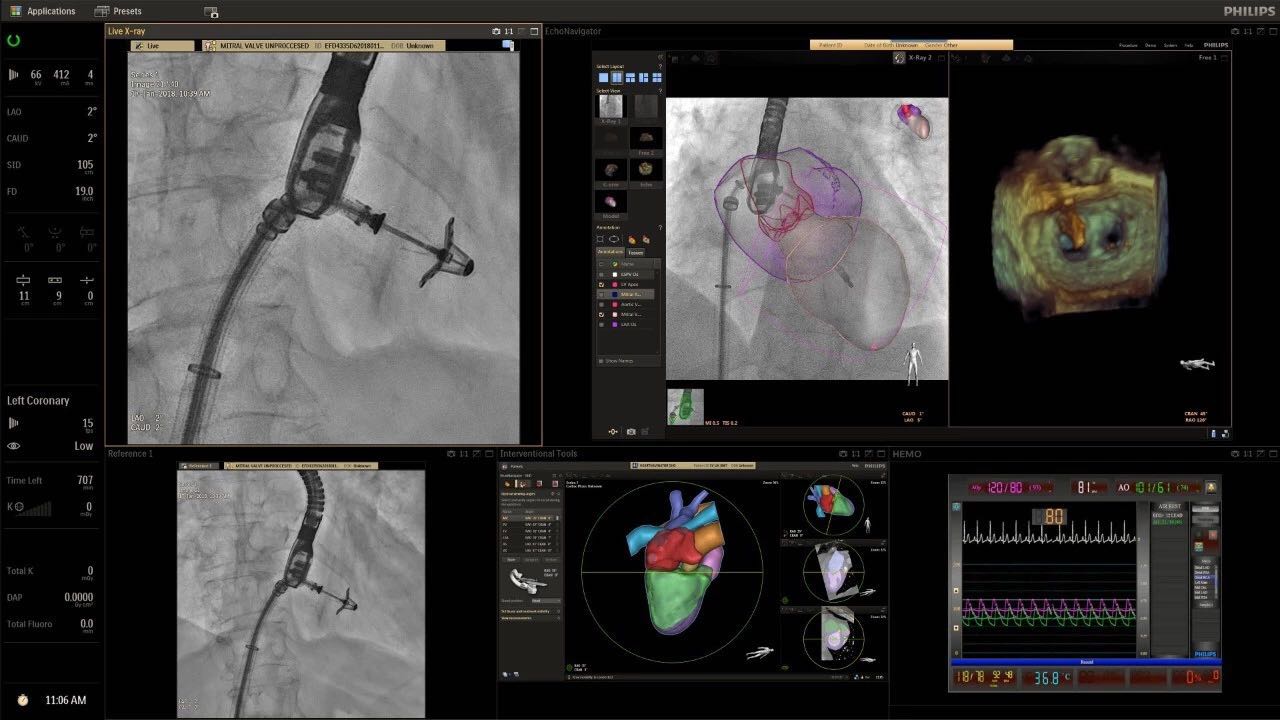

在日益復(fù)雜的干預(yù)期間,臨床醫(yī)生需要快速、輕松地可視化關(guān)鍵解剖結(jié)構(gòu)并確定手術(shù)過(guò)程中患者的變化。2019年1月17日,飛利浦宣布推出采用FlexArm的Azurion 7 C20,旨在提高圖像引導(dǎo)程序的定位靈活性。

帶有FlexArm的Azurion 7 C20 包含一系列創(chuàng)新技術(shù),使臨床醫(yī)生可以更輕松地在整個(gè)患者身上進(jìn)行二維和三維成像。當(dāng)臨床醫(yī)生移動(dòng)系統(tǒng)時(shí),圖像光束自動(dòng)保持與患者的對(duì)準(zhǔn),允許更一致的可視化并使他們能夠?qū)⒆⒁饬性谥委熒稀?/span>

(FlexArm C型臂可以沿著工作臺(tái)的兩側(cè)提供偏心成像。這允許醫(yī)生在左臂或右臂上進(jìn)行徑向進(jìn)入病例,完全或部分伸展,而無(wú)需移動(dòng)患者或樞轉(zhuǎn)桌子。X射線束與手臂保持對(duì)齊,以促進(jìn)其整個(gè)長(zhǎng)度的平滑導(dǎo)航,而無(wú)需進(jìn)行持續(xù)調(diào)整。)

飛利浦表示,采用FlexArm設(shè)計(jì)的Azurion 7 C20可提供卓越的靈活性和直觀的控制。該系統(tǒng)由智能運(yùn)動(dòng)引擎驅(qū)動(dòng),可在八個(gè)不同的軸上移動(dòng),所有這些軸均由其單個(gè)“Axsys”控制器控制。臨床醫(yī)生的模擬測(cè)試表明,該系統(tǒng)有可能顯著減少患者,工作人員和設(shè)備的重新定位,從而改善微創(chuàng)手術(shù)的可及性,包括通過(guò)患者手腕進(jìn)入身體的手術(shù)(橈動(dòng)脈入路),并降低患者的風(fēng)險(xiǎn)。無(wú)意中拔出電線和管子,以及節(jié)省大量時(shí)間。該系統(tǒng)非常適合混合手術(shù)室(OR),可滿足一個(gè)房間內(nèi)的多種專業(yè)需求,例如手術(shù)和血管內(nèi)手術(shù)的組合。

FlexArm在不少于8軸的情況下旋轉(zhuǎn),從而創(chuàng)建幾乎無(wú)限的靈活性來(lái)執(zhí)行成像,從頭部到腳部在左側(cè)和右側(cè)進(jìn)行2D和3D可視化。圖像光束保持與患者對(duì)齊,允許在旋轉(zhuǎn)或角度期間更好地可視化解剖結(jié)構(gòu)。使用Axsys運(yùn)動(dòng)控制系統(tǒng)輕松操作支架。